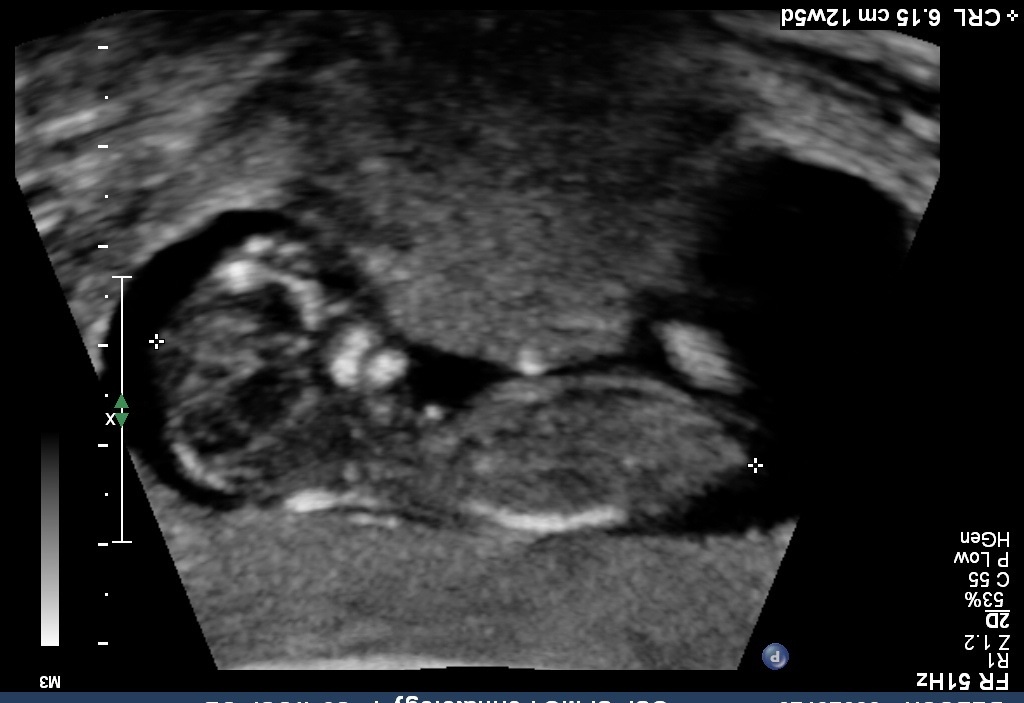

I know it is early and this isn't a great pic, but any thoughts on gender? I was 12 weeks, 1 day.

Yeah I wasn't given any good profile shots.:-/ Here's what I have...Attachment 12408Attachment 12409Attachment 12410

Sure let me try...Attachment 12423Attachment 12424Attachment 12425Attachment 12426